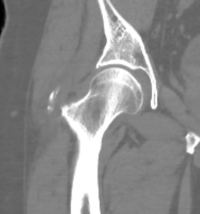

55-åring med snabbt insättande mycket kraftig smärta i höger höft, spontant återställd efter ett par dagar

• Kan i undantagsfall sätta sig i andra muskler, exempelvis vid höft - "kalkhöft"